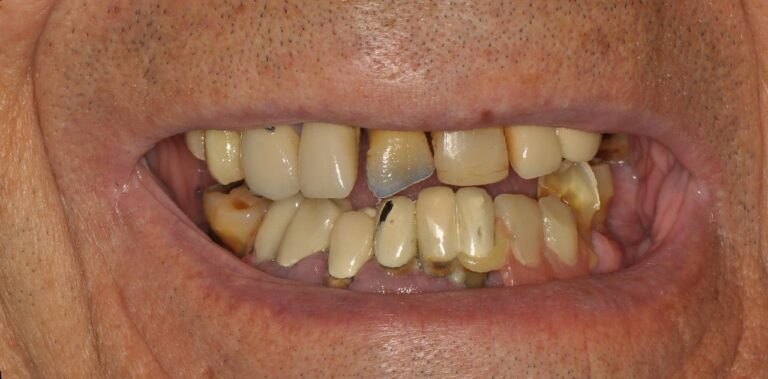

Case 5 – Panos with extreme maxillary atrophy